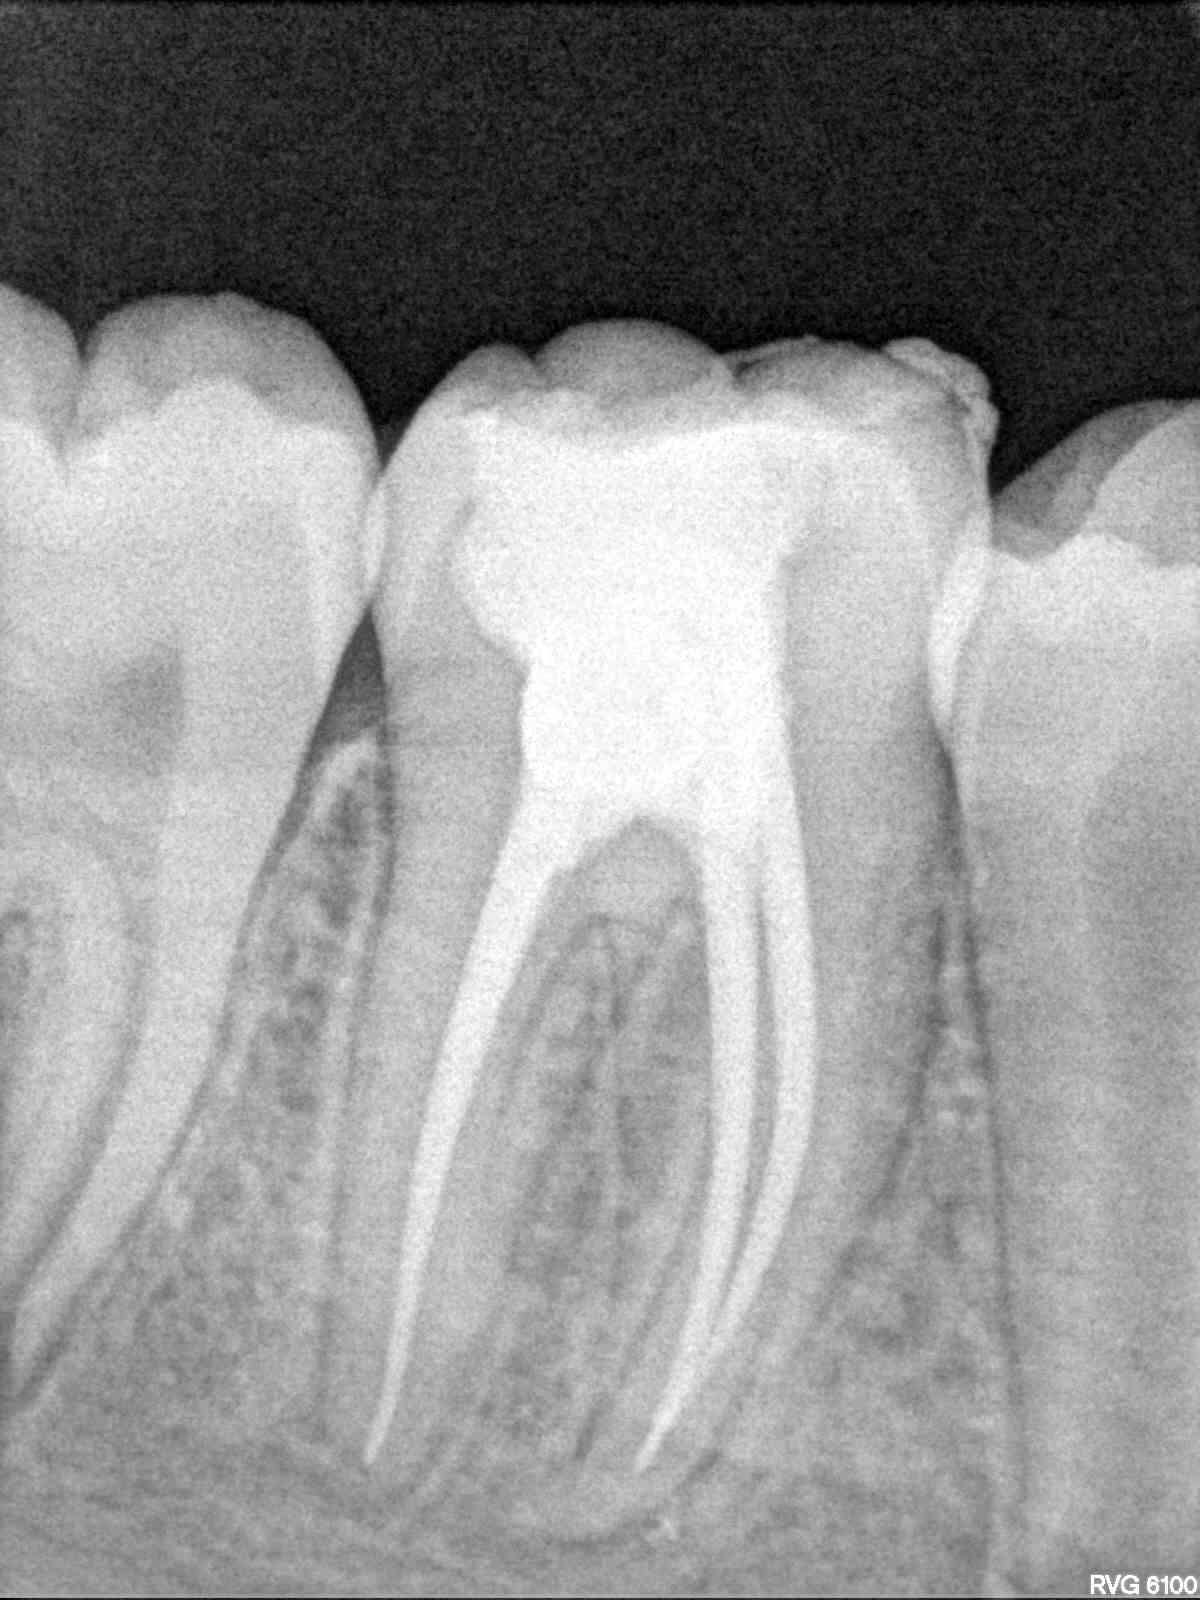

Pour l'endo au départ du post elle est très bien c'est à mon avis une histoire de contraste.

Je vois que tu as le meme logiciel d'imagerie que le mien sers toi de la balance de contraste du panneau de controle !